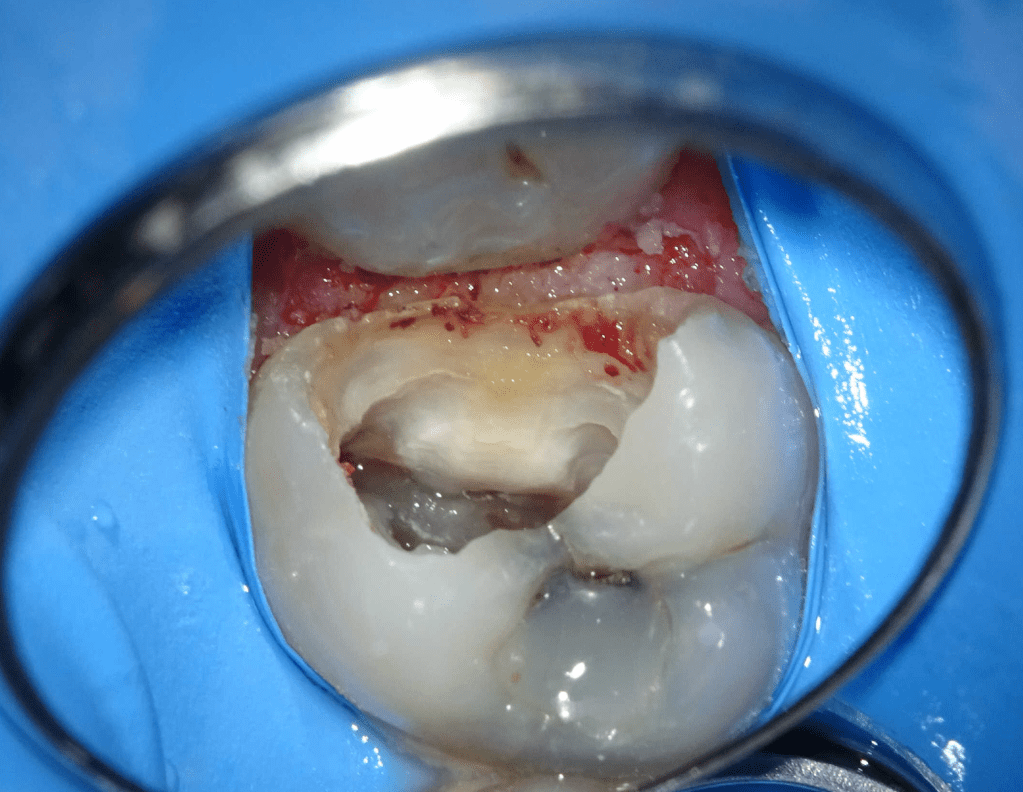

Reconstrucción preendodóntica

Reco pared vesticular